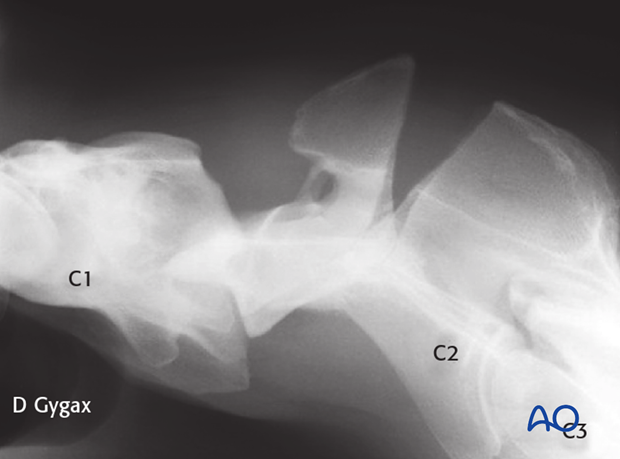

A 7-year-old Warmblood gelding was admitted with a 3-week history of neck stiffness. The horse had an acute onset of neck stiffness with no known trauma. According to the owner, the horse had initial mild signs of ataxia and weakness in the hind limbs.

Marked swelling was detectable in the proximal third of the neck at the level of the second cervical vertebra (C2).

The fracture was repaired using a 7-hole 4.5mm DCP. Optimal positioning of the plate and the length of the screws were facilitated by fluoroscopy.